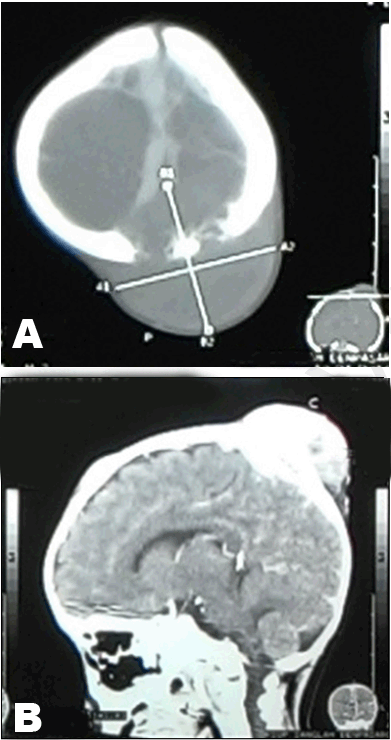

Chest X-ray revealed a solitary nodule on the right paracardial region suspicious for metastasis of pulmonary nodular type (differential diagnosis: primary mass) and the destruction of the right scapular bone very likely the process of metastasis (Figure 2). Head computed tomography (CT) scan revealed soft tissue masses on left frontoparietal and left parietooccipital region with administration of contrast showed enhancement. The masses looked destructed bone underneath that seems to infiltrate the brain parenchyma (Figure 3).

Figure 3: (A) Axial section of head computed tomography scan showed masses destructed bone underneath, (B) Sagital section of head computed tomography scan with contrast showed masses at frontoparietal and parietooccipital region with enhancement and bone destruction.